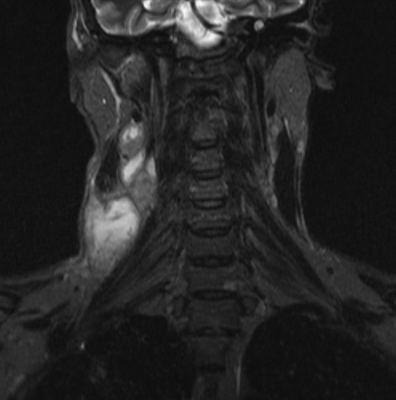

Результат МР-сканирования мягких тканей шеи

МРТ грудного отдела позвоночника в коронарной проекции